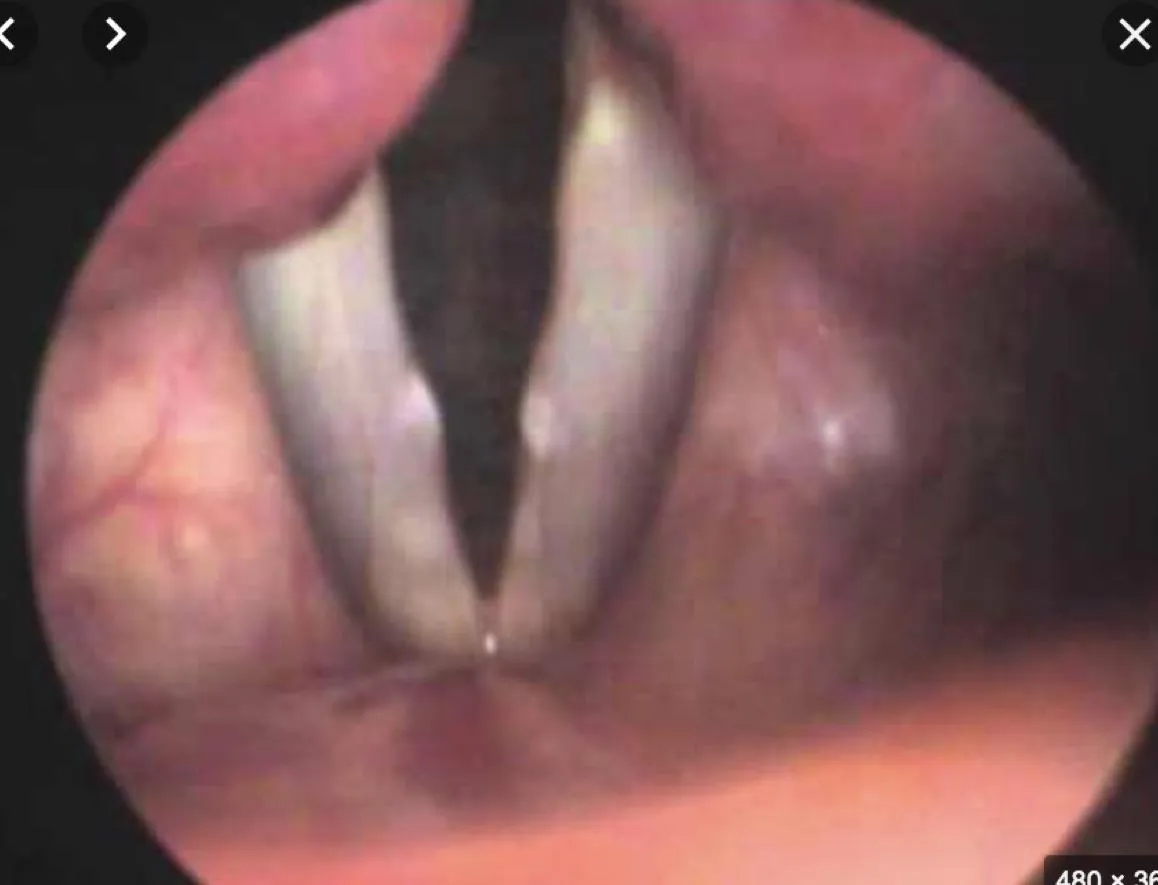

Subglottic Stenosis

- Question: 8 months old baby post open heart surgery at age of 1 month, kept intubated for 1 week post operative referred to the clinic with stridor, underwent direct laryngobronchoscopy and the finding displayed in the picture.

- Answer:

- A- What is the diagnosis?

- Subglottic stenosis

- B- What is the type of stridor expected to be heard in this case?

- Biphasic